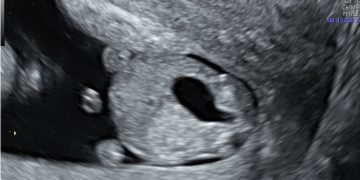

Casi del Mese di Dicembre 2024

Cari soci, finalmente on line le soluzioni dei casi del mese di Dicembre. Grazie a Sara Zullino e Mara Albanese!! Caso 1 - video [pdf-embedder url="https://www.sieog.it/wp-content/uploads/2024/12/Casodelmese_Dicembre2024caso-risposte_gineco.pdf"...